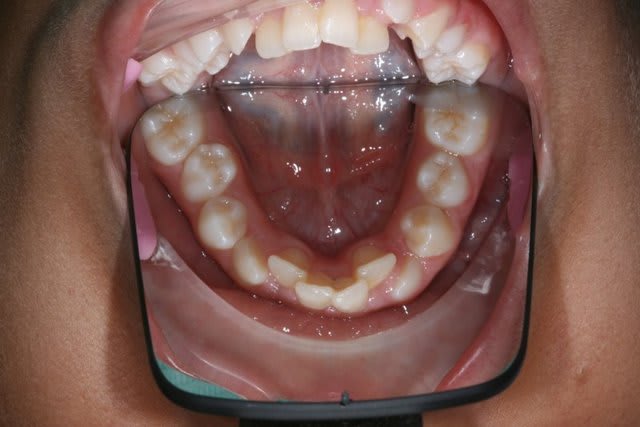

Img 0812 mvp6i0 - Eugenol

jeamba

25/04/2009 à 15h10

Premier essai.

25/04/2009 à 15h13

Suite.

La conservation du lee way me paraît une solution raisonnable.

En fait c'est un cas qui date de plus de 4ans et je n'ai plus les photos complètes du cas car je ne stoque pas longtemps sur mon ordi pour ne pas trop surcharger; etj'ai donc garder ces trois photos comme modèle d'explication aux patients.

Entre la première et la deuxième photo il n'y a eu q'un arc de base pour maintenir la dimention antéro-postérieure et ensuite un sectionnel aprés la chute des dents de lait.

J'ai toujours utilisé le lee way chaque fois que j'ai eu la chance d'avoir le patient aussi jeune. Aujourd'hui il est vrai que j'essaye de faire autre chose mais cette façon de faire marchait assez bien.